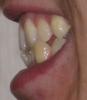

persona Опубликовано 12 октября, 2008 Автор Поделиться Опубликовано 12 октября, 2008 (изменено) Кроме того, проходил КТ. Выкладываю несколько срезов в области клыка. Изменено 12 октября, 2008 пользователем persona Ссылка на комментарий

Force Опубликовано 12 октября, 2008 Поделиться Опубликовано 12 октября, 2008 Кроме того, проходил КТ. Выкладываю несколько срезов в области клыка. А кто из врачей делал Вам трг перед планированием с расчетом? а расчет моделей делали? Ссылка на комментарий

Премоляр Опубликовано 14 октября, 2008 Поделиться Опубликовано 14 октября, 2008 Хм, честно говоря, у меня тоже небольшие сомнения вызывала возможность отцентровки при таком лечении.Т.е. вы за вариант лечения с имплантом? Но в этом случае точно придется удалять ретинированный клык, а при 2-ом плане лечения его можно было бы не трогать.Поставить в зубную дугу ретенир.клык будет очень очень травматично и сложно.И оставлять "просто так" клык тоже нельзя-т.к. со временем вокруг клыка может образоваться киста.(а может и нет...). Возможно целесообразнее удалить нижнюю 4ку справа(коррекция центра) и выравнивание зубов на вер.чел+последующая реставрация 4 ки сверху справа. И еще-сделать КТ для определения точной локализации ретенир.зуба(решения вопроса о его дальнейшей судьбе) Ссылка на комментарий

persona Опубликовано 14 октября, 2008 Автор Поделиться Опубликовано 14 октября, 2008 Поставить в зубную дугу ретенир.клык будет очень очень травматично и сложно.И оставлять "просто так" клык тоже нельзя-т.к. со временем вокруг клыка может образоваться киста.(а может и нет...). Возможно целесообразнее удалить нижнюю 4ку справа(коррекция центра) и выравнивание зубов на вер.чел+последующая реставрация 4 ки сверху справа. И еще-сделать КТ для определения точной локализации ретенир.зуба(решения вопроса о его дальнейшей судьбе)Спасибо большое за ответ. Только я не совсем понял насчет 4-ок. Может имелись в виду не правые, а левые 4-ки? Если так, то это получится в точности 2-ой вариант из тех, что я написал в первом посте. Ретинированный клык все врачи кроме одного рекомендуют не трогать, т.к. пока не беспокоит и корней других зубов вроде не задевает. КТ я сделал. Несколько срезов выложены во 2-ом посте. Если надо, могу выложить еще, но они все горизонтальные. Также есть еще снимок с 3-мерным изображением, но не думаю, что там лучше видно. Ссылка на комментарий